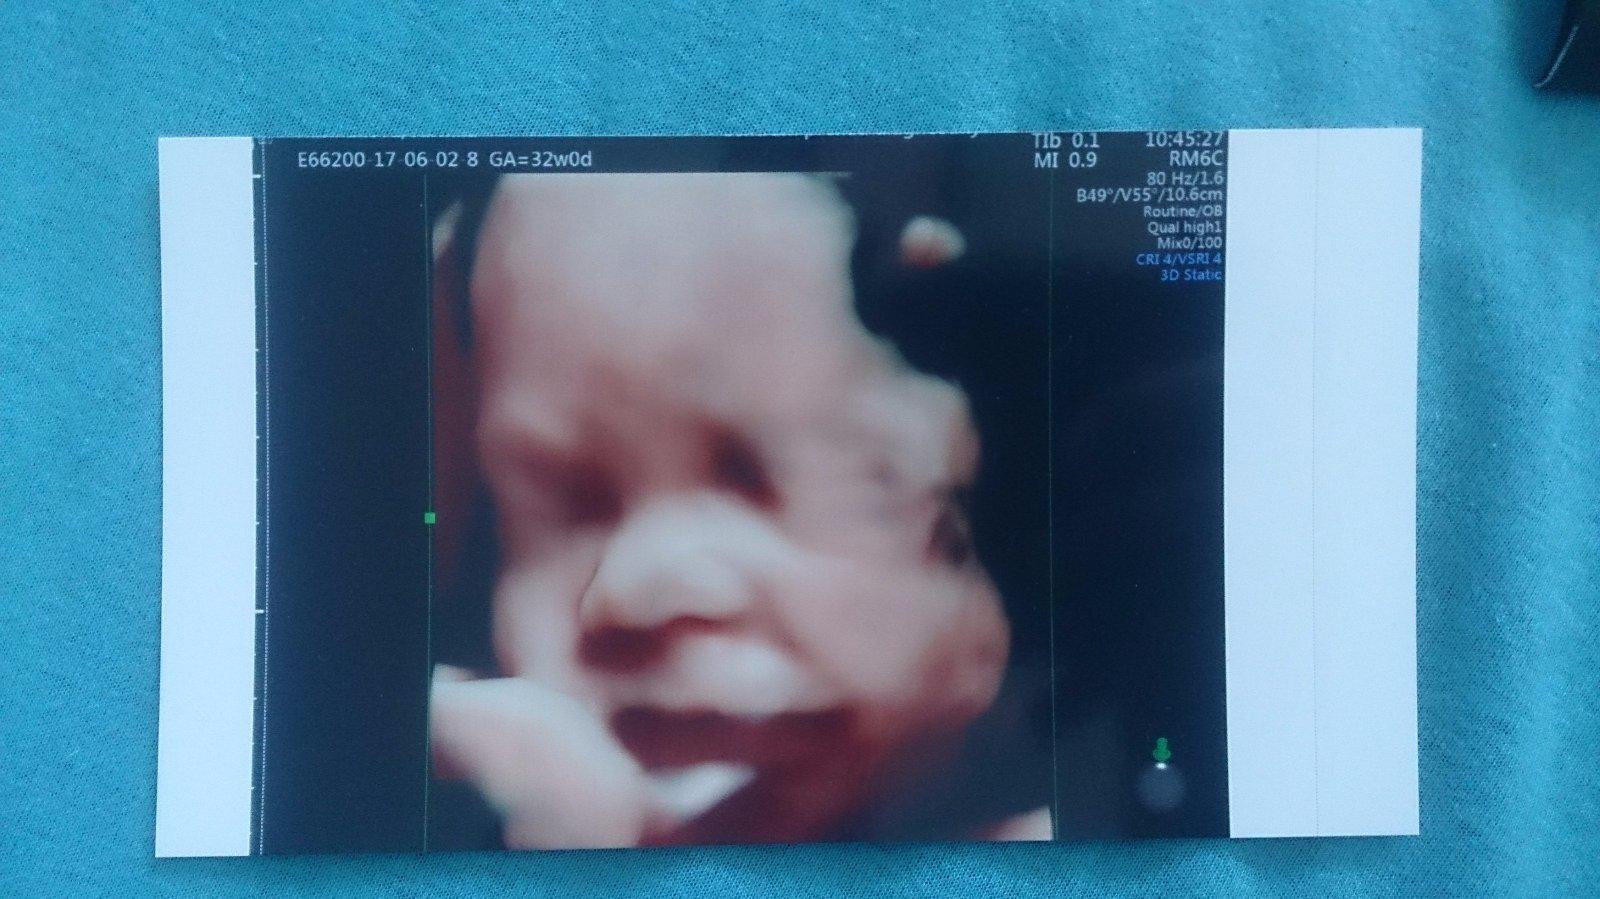

@olylili a toto je nasa bublinka...konecne sa nam aj ukazala 🙂

@jarunka102 jeeeeeeeezisi nádherná ako sa usmieva 😊 krásna fotka

@jarunka102 nádherná princezná 👧❤

@jarunka102 krasna je😉